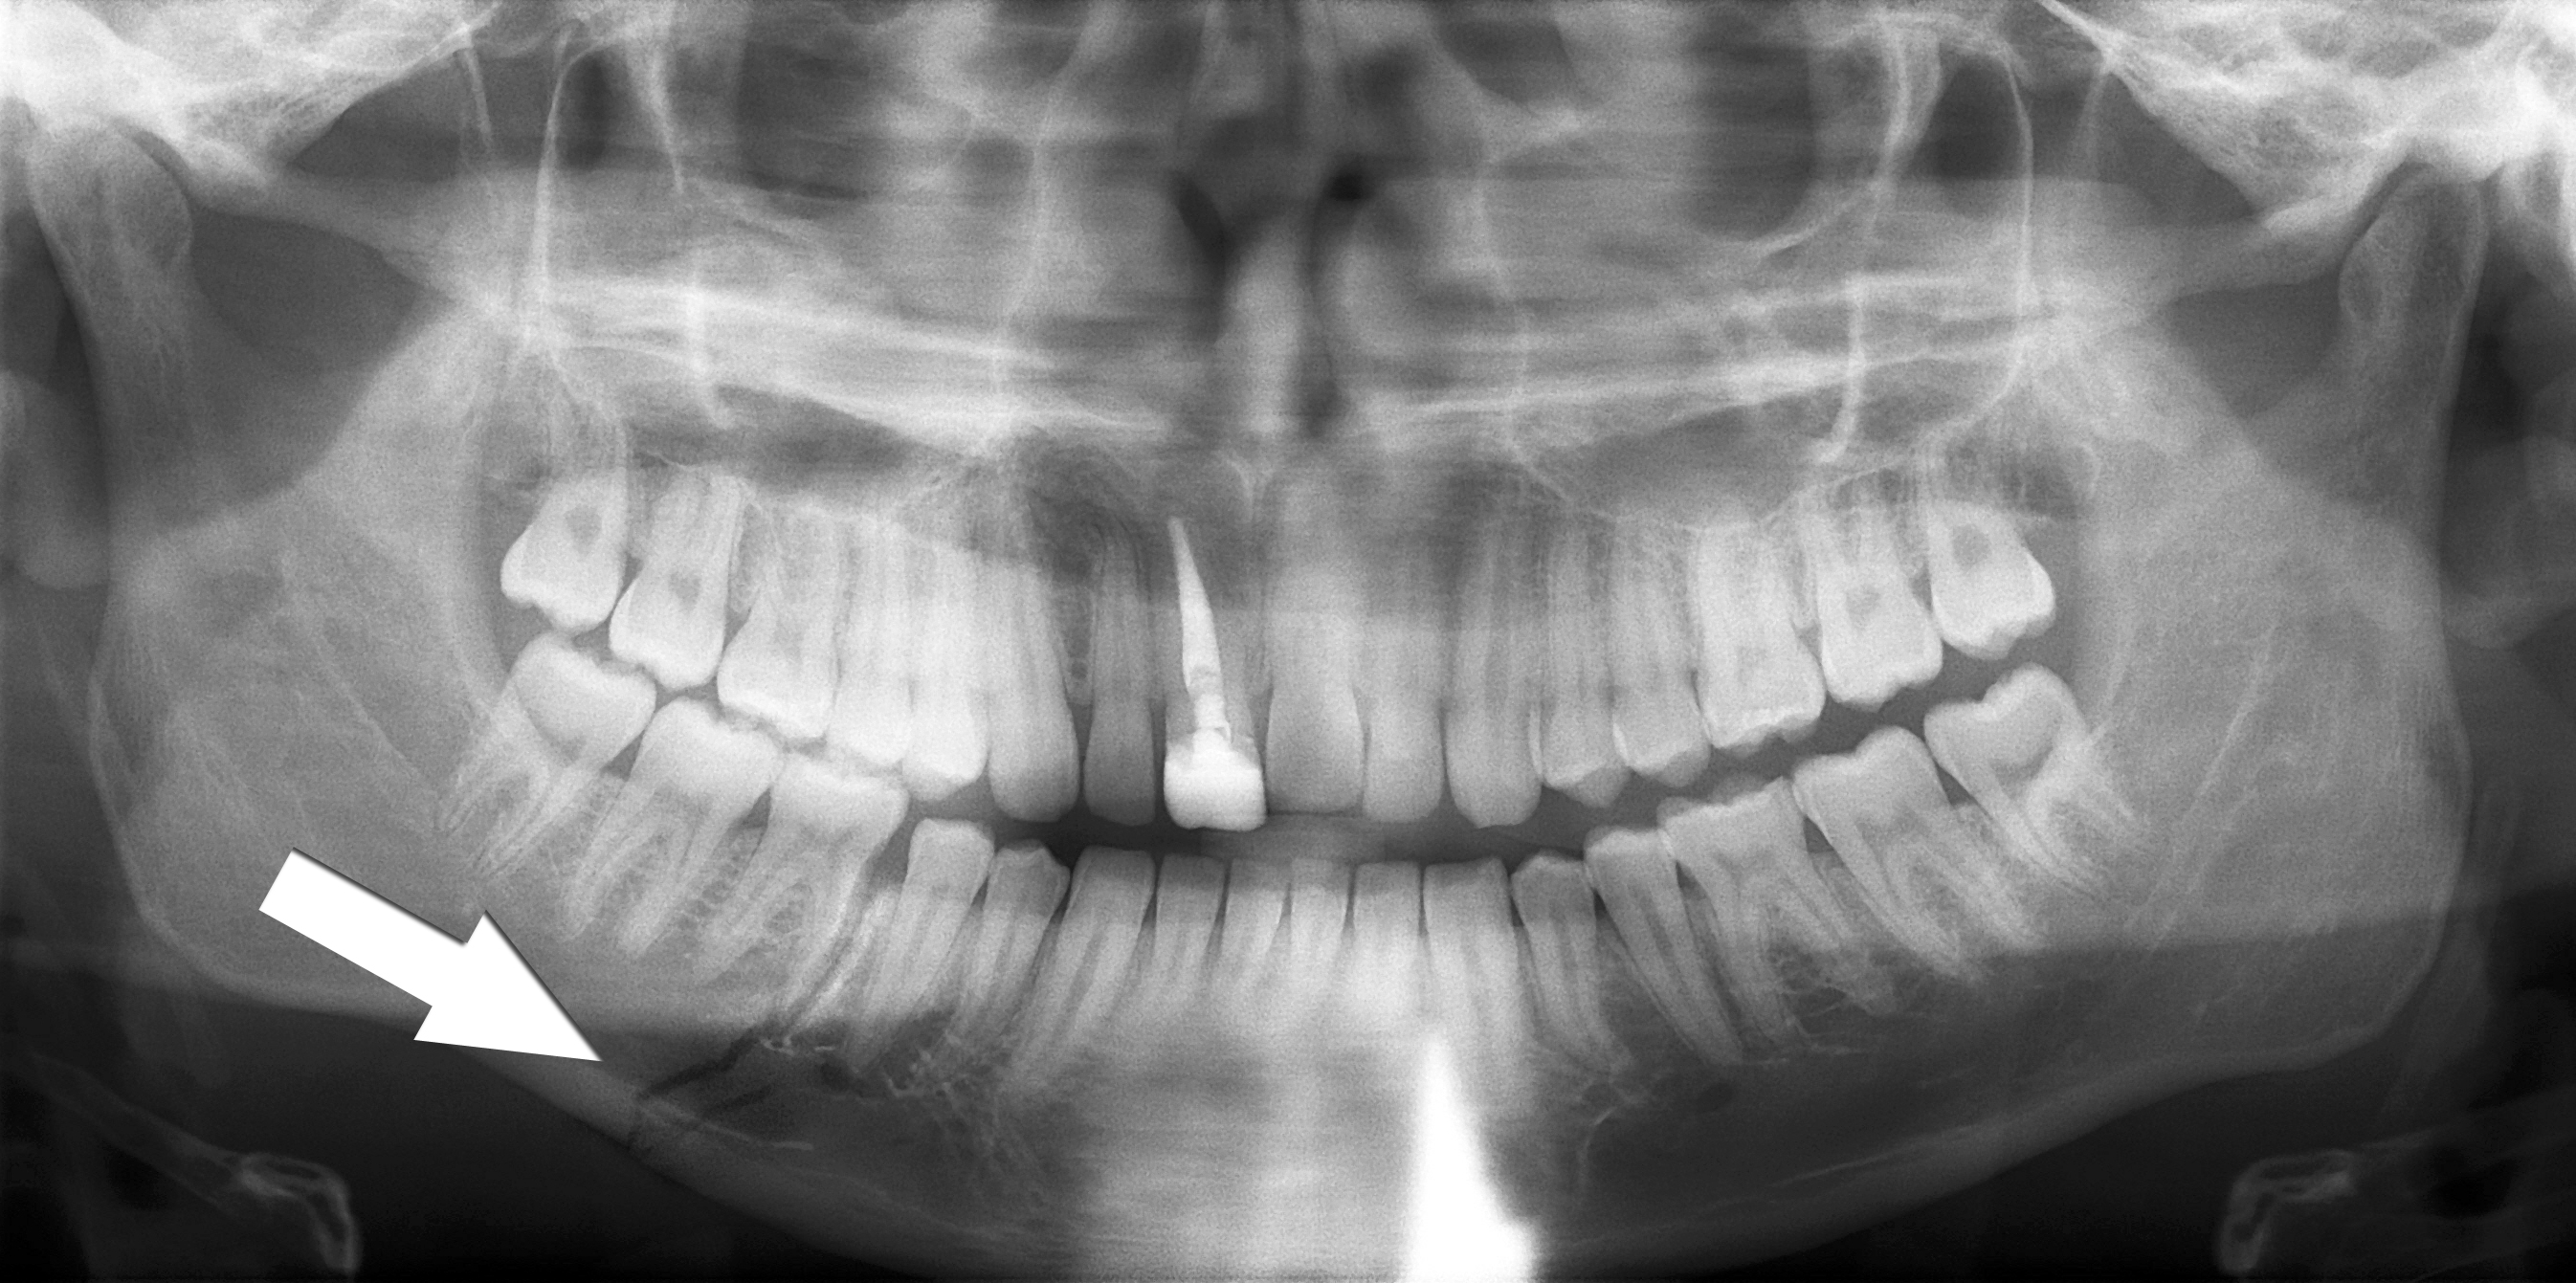

Digital Panoramic X-Ray

An Orthopantomogram (OPG), also known as an "orthopantogram" or "panorex", is a panoramic scanning dental X-ray of the upper and lower jaw. It shows a two-dimensional view of a half-circle from ear to ear. OPGs are used by dentists to provide information on :

• Impacted wisdom teeth

• Periodontal bone loss

• Finding the source of dental pain

• Assessment for the placement of dental implants

• Orthodontic assessment